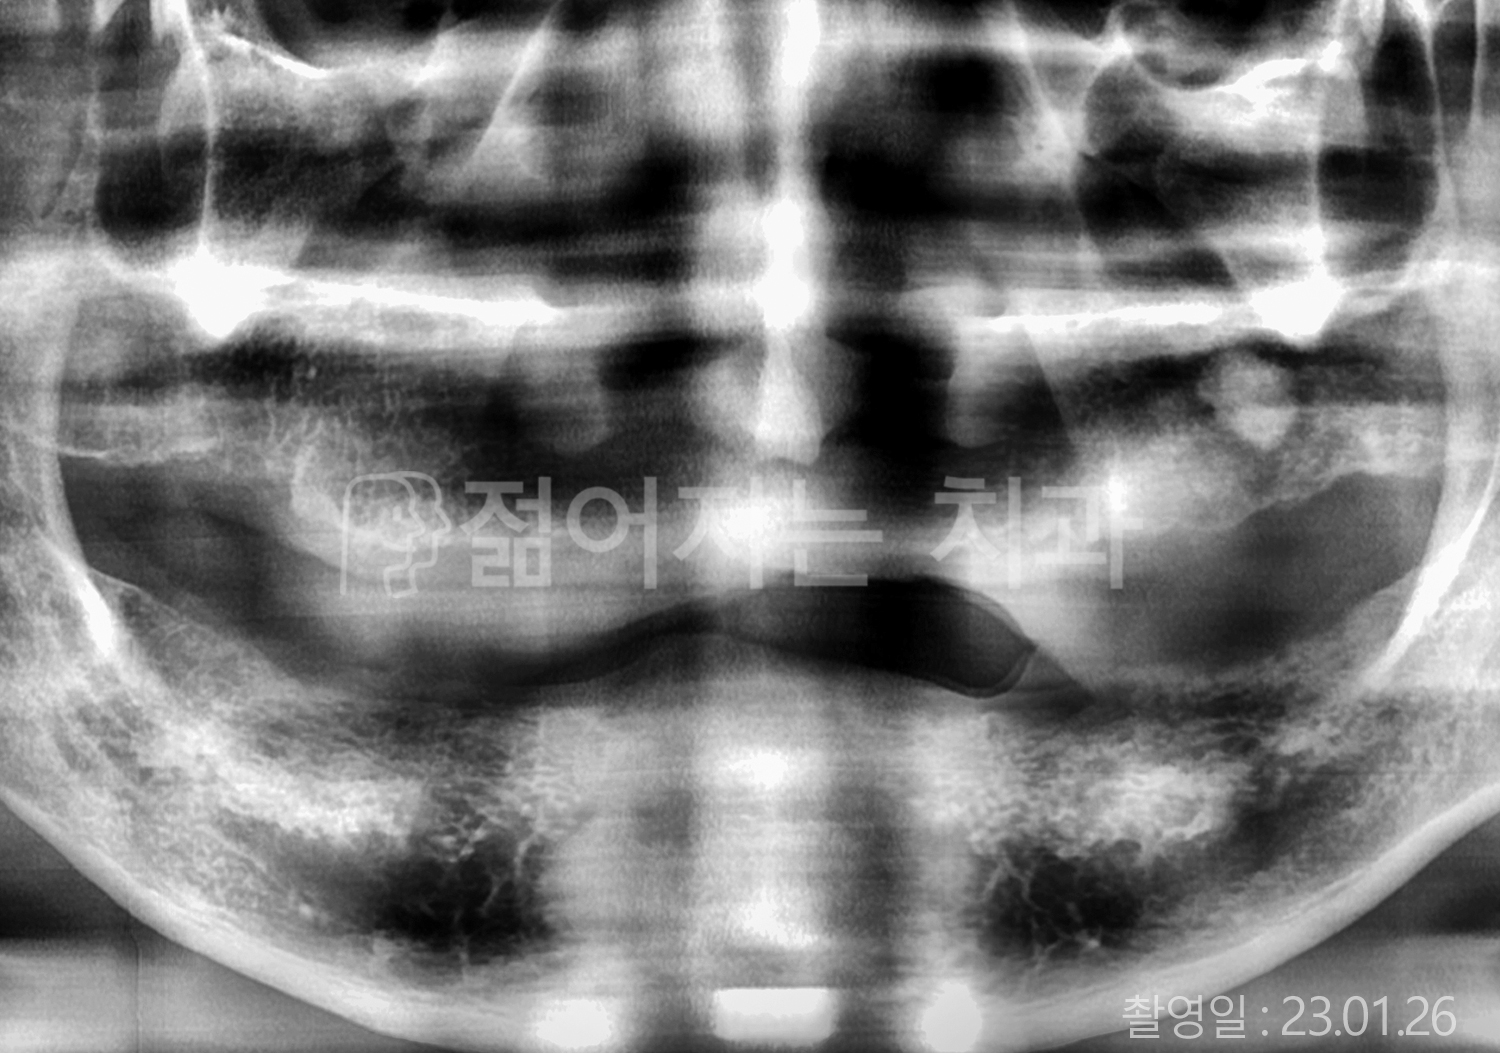

치료사례(치아)

• 80대 전체치아 10개 이상 임플란트

• 60대 고혈압, 당뇨, 고지혈증 전체치아 10개 이상 임플란트

• 60대 전체치아 10개 이상 임플란트

• 60대 고혈압, 고지혈증 전체치아 10개 이상 임플란트

• 50대 고혈압, 당뇨, 고지혈증 전체치아 10개 이상 임플란트

• 70대 골다골증, 파킨스병 전체치아 10개 이상 임플란트

• 40대 전체치아 10개 이상 임플란트

• 60대 골다골증 전체치아 10개 이상 임플란트

• 40대 고혈압 전체치아 10개 이상 임플란트

• 50대 전체치아 10개 이상 임플란트

• 70대 전체치아 10개 이상 임플란트

위 사진의 저작권은 젊어지는 치과에 있습니다.

본 사진은 환자분의 동의 하에 게재 되었습니다.

* 위 사진은 동일 조건에서 촬영 되었습니다. / 모든 치료에는 부작용이 발생할 수 있습니다.